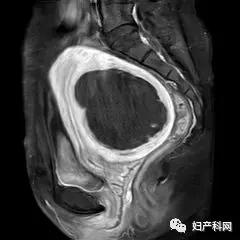

术后1周复查MRI,如下: